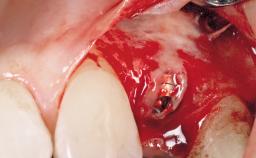

Late Flapless Placement of an Implant in a Maxillary Left Central Incisor Site

A 39-year-old male patient presented with a chief complaint of discomfort and gingival discoloration around his maxillary left central incisor. He was in good general health and was a non-smoker. His past dental history was significant because of the traumatic fracture of tooth 21 in a sporting accident at age 13. Initial dental treatment included endodontic therapy and a full-coverage restoration. The patient became symptomatic 5 years later, when structural failure of the tooth resulted in the dislodgment of the crown. Endodontic retreatment, apical surgery, and post-and-core restoration were performed.

Bone Augmentation Horizontal|Staged

Augmentation Materials Xenogenous|Membrane

Soft Tissue Grafting Simultaneous

Bone Volume Deficient horizontally, requiring prior grafting